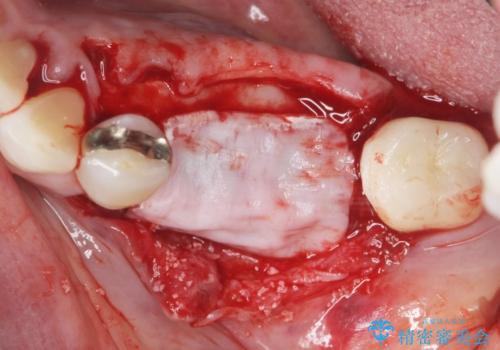

舌側にある大きな骨隆起を除去するとともに、除去した骨と人工骨を用いてインプラント周囲の骨を造成します。

自家骨と人工骨による骨造成は、長期的に見て安定し吸収が少ないとされる骨の造成法です。

インプラント周囲に、必要十分な骨を作ることが長期渡りインプラントにトラブルを起こしにくい鍵となります。